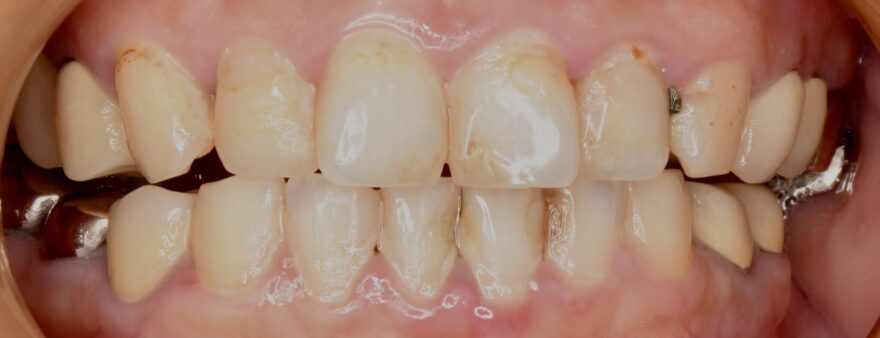

どこで噛んでいいか分からない:40代女性

Before

After

治療内容

全体的な噛み合わせが狂ってしまい、どこで噛んでいいか分からない状態でした。

8本のインプラント治療と16本のセラミック治療で、しっかり上下の歯が噛み合う状態にしました。